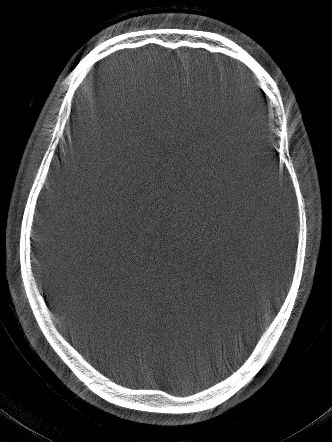

Using the test patient, the network behavior for motion exceeding the RPE of the training process is inspected in an inverse crime scenario. The simulated motion trajectory is depicted in Fig. 2 together with the estimated motion trajectory after optimization using the network as IQM (cf. Eq. 1). For each iteration of the optimization process the network predicted RPE together with the corresponding Gt RPE is depicted. While the RPE is underestimated within the first iterations, the proportionality is still kept, guiding the optimization to a motion free reconstruction.

Figure 2: Left: Network-predicted and Gt RPE in each iteration step of the optimization. Right: Simulated motion trajectory and estimated motion trajectory after optimization.